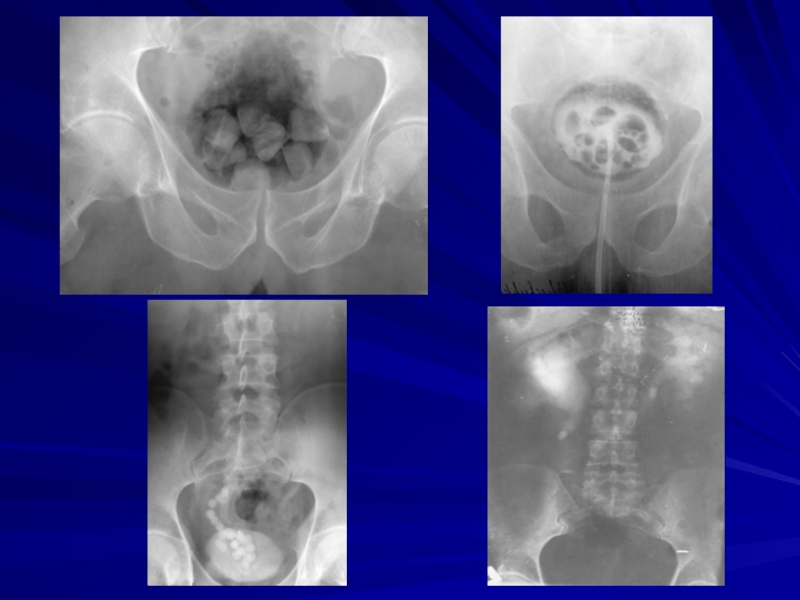

Слайд 13На разрезе почки виден большой коралловидный конкремент, расположенный почечной лоханке (в

центре вверху) Более мелкий камень определяется слева (выделен кружком)